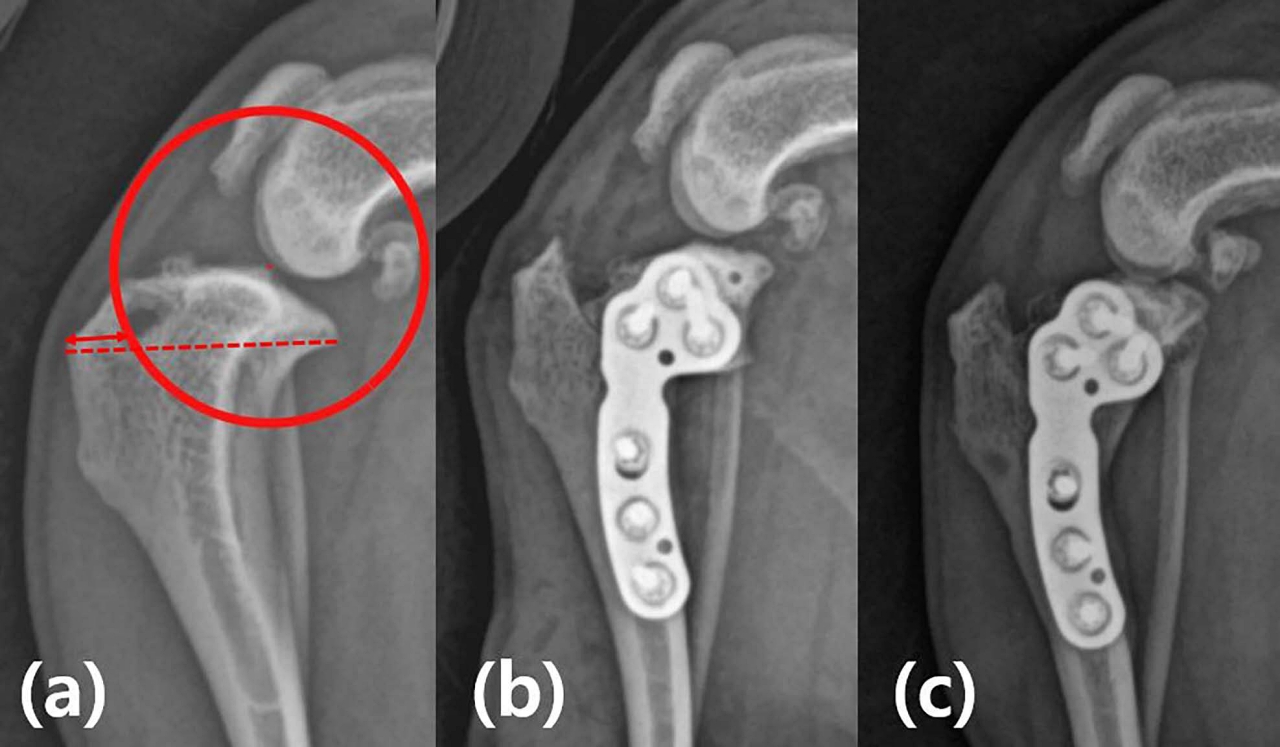

두 병원에서 실시한 TPLO에는 10mm 반경의 원형 절골술이 적용됐다. 정강뼈거친면(경골 조면, tibial tuberosity)의 폭을 25% 이상 보존하도록 수술을 계획했다. 수술은 강병재 교수와 정창수 원장이 집도했다.

3.2kg 말티즈 환자에서 실시한 TPLO의 수술 전 계획 및 술후 방사선 사진